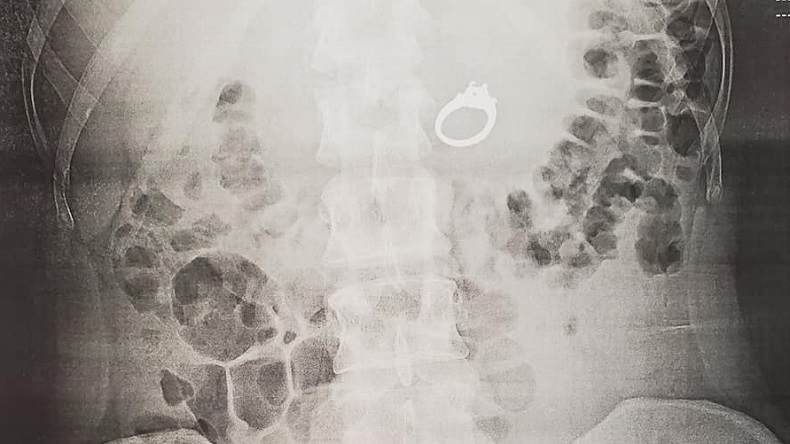

La pareja fue al hospital y después que las radiografías confirmaran que el anillo estaba en su estómago le hicieron una endoscopia para extraerlo, lo que Jenna agradeció pues no quería expulsarlo "de forma natural".